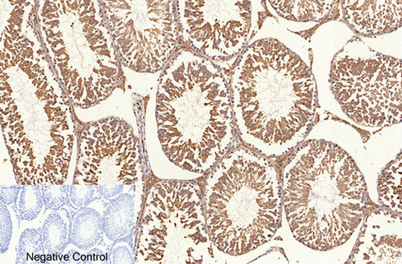

ÕŠ«õ┐ĪńöĄĶäæń½»ÕÆ©Ķ»ó

Õģ│µ│©ÕŠ«õ┐ĪÕģ¼õ╝ŚÕÅĘ

ÕŠ«õ┐Īµē½õĖƵē½Ķ┐×Õ┐ÖÕÆ©Ķ»ó

ÕŠ«õ┐Īµē½õĖƵē½Ķ┐×Õ┐ÖÕÆ©Ķ»ó